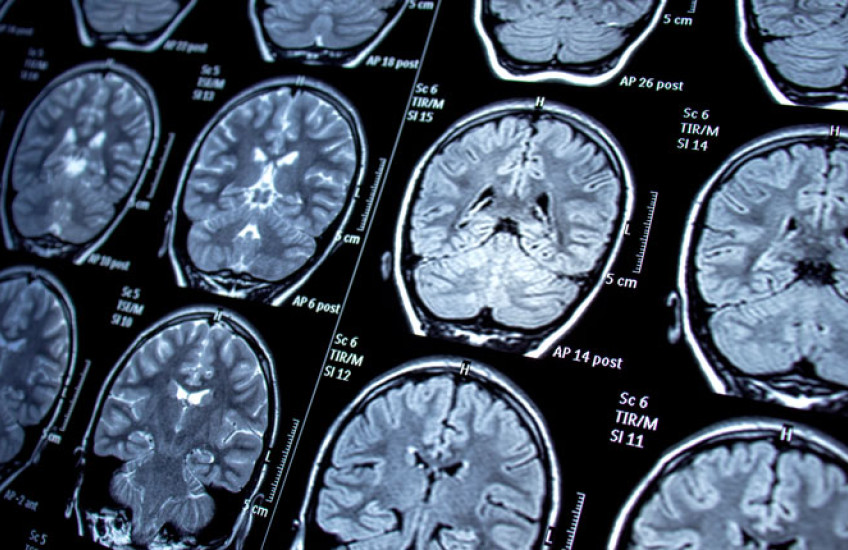

To uncover somatic mutations, Khoshkhoo and colleagues performed a case-control genetic association study, analyzing DNA from brain tissue samples collected from 105 patients with epilepsy and 30 controls between 1988 and 2019.

The team sequenced portions of the genome coding for proteins (whole exome sequencing) and looked at specific locations in the genome (gene-panel sequencing), with each genomic region sequenced more than 500 times on average.